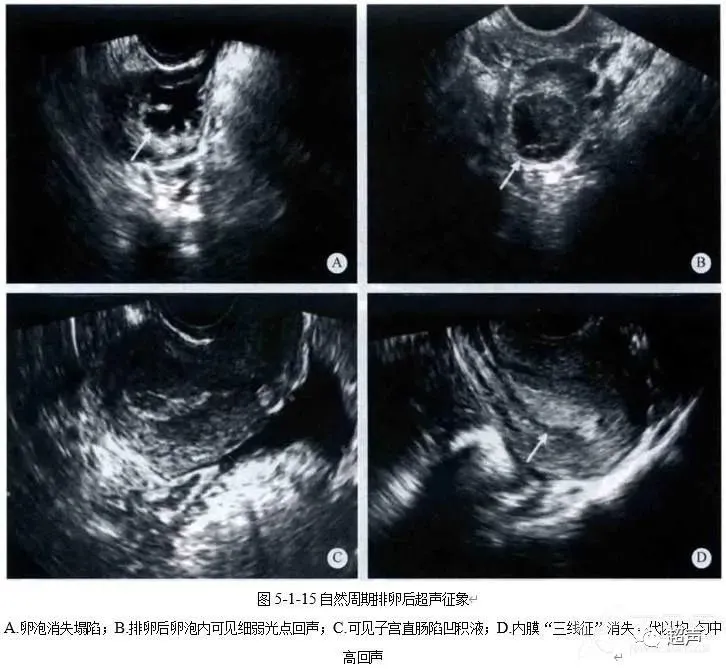

健康科普 | 好“孕”第一步——卵泡的超声监测